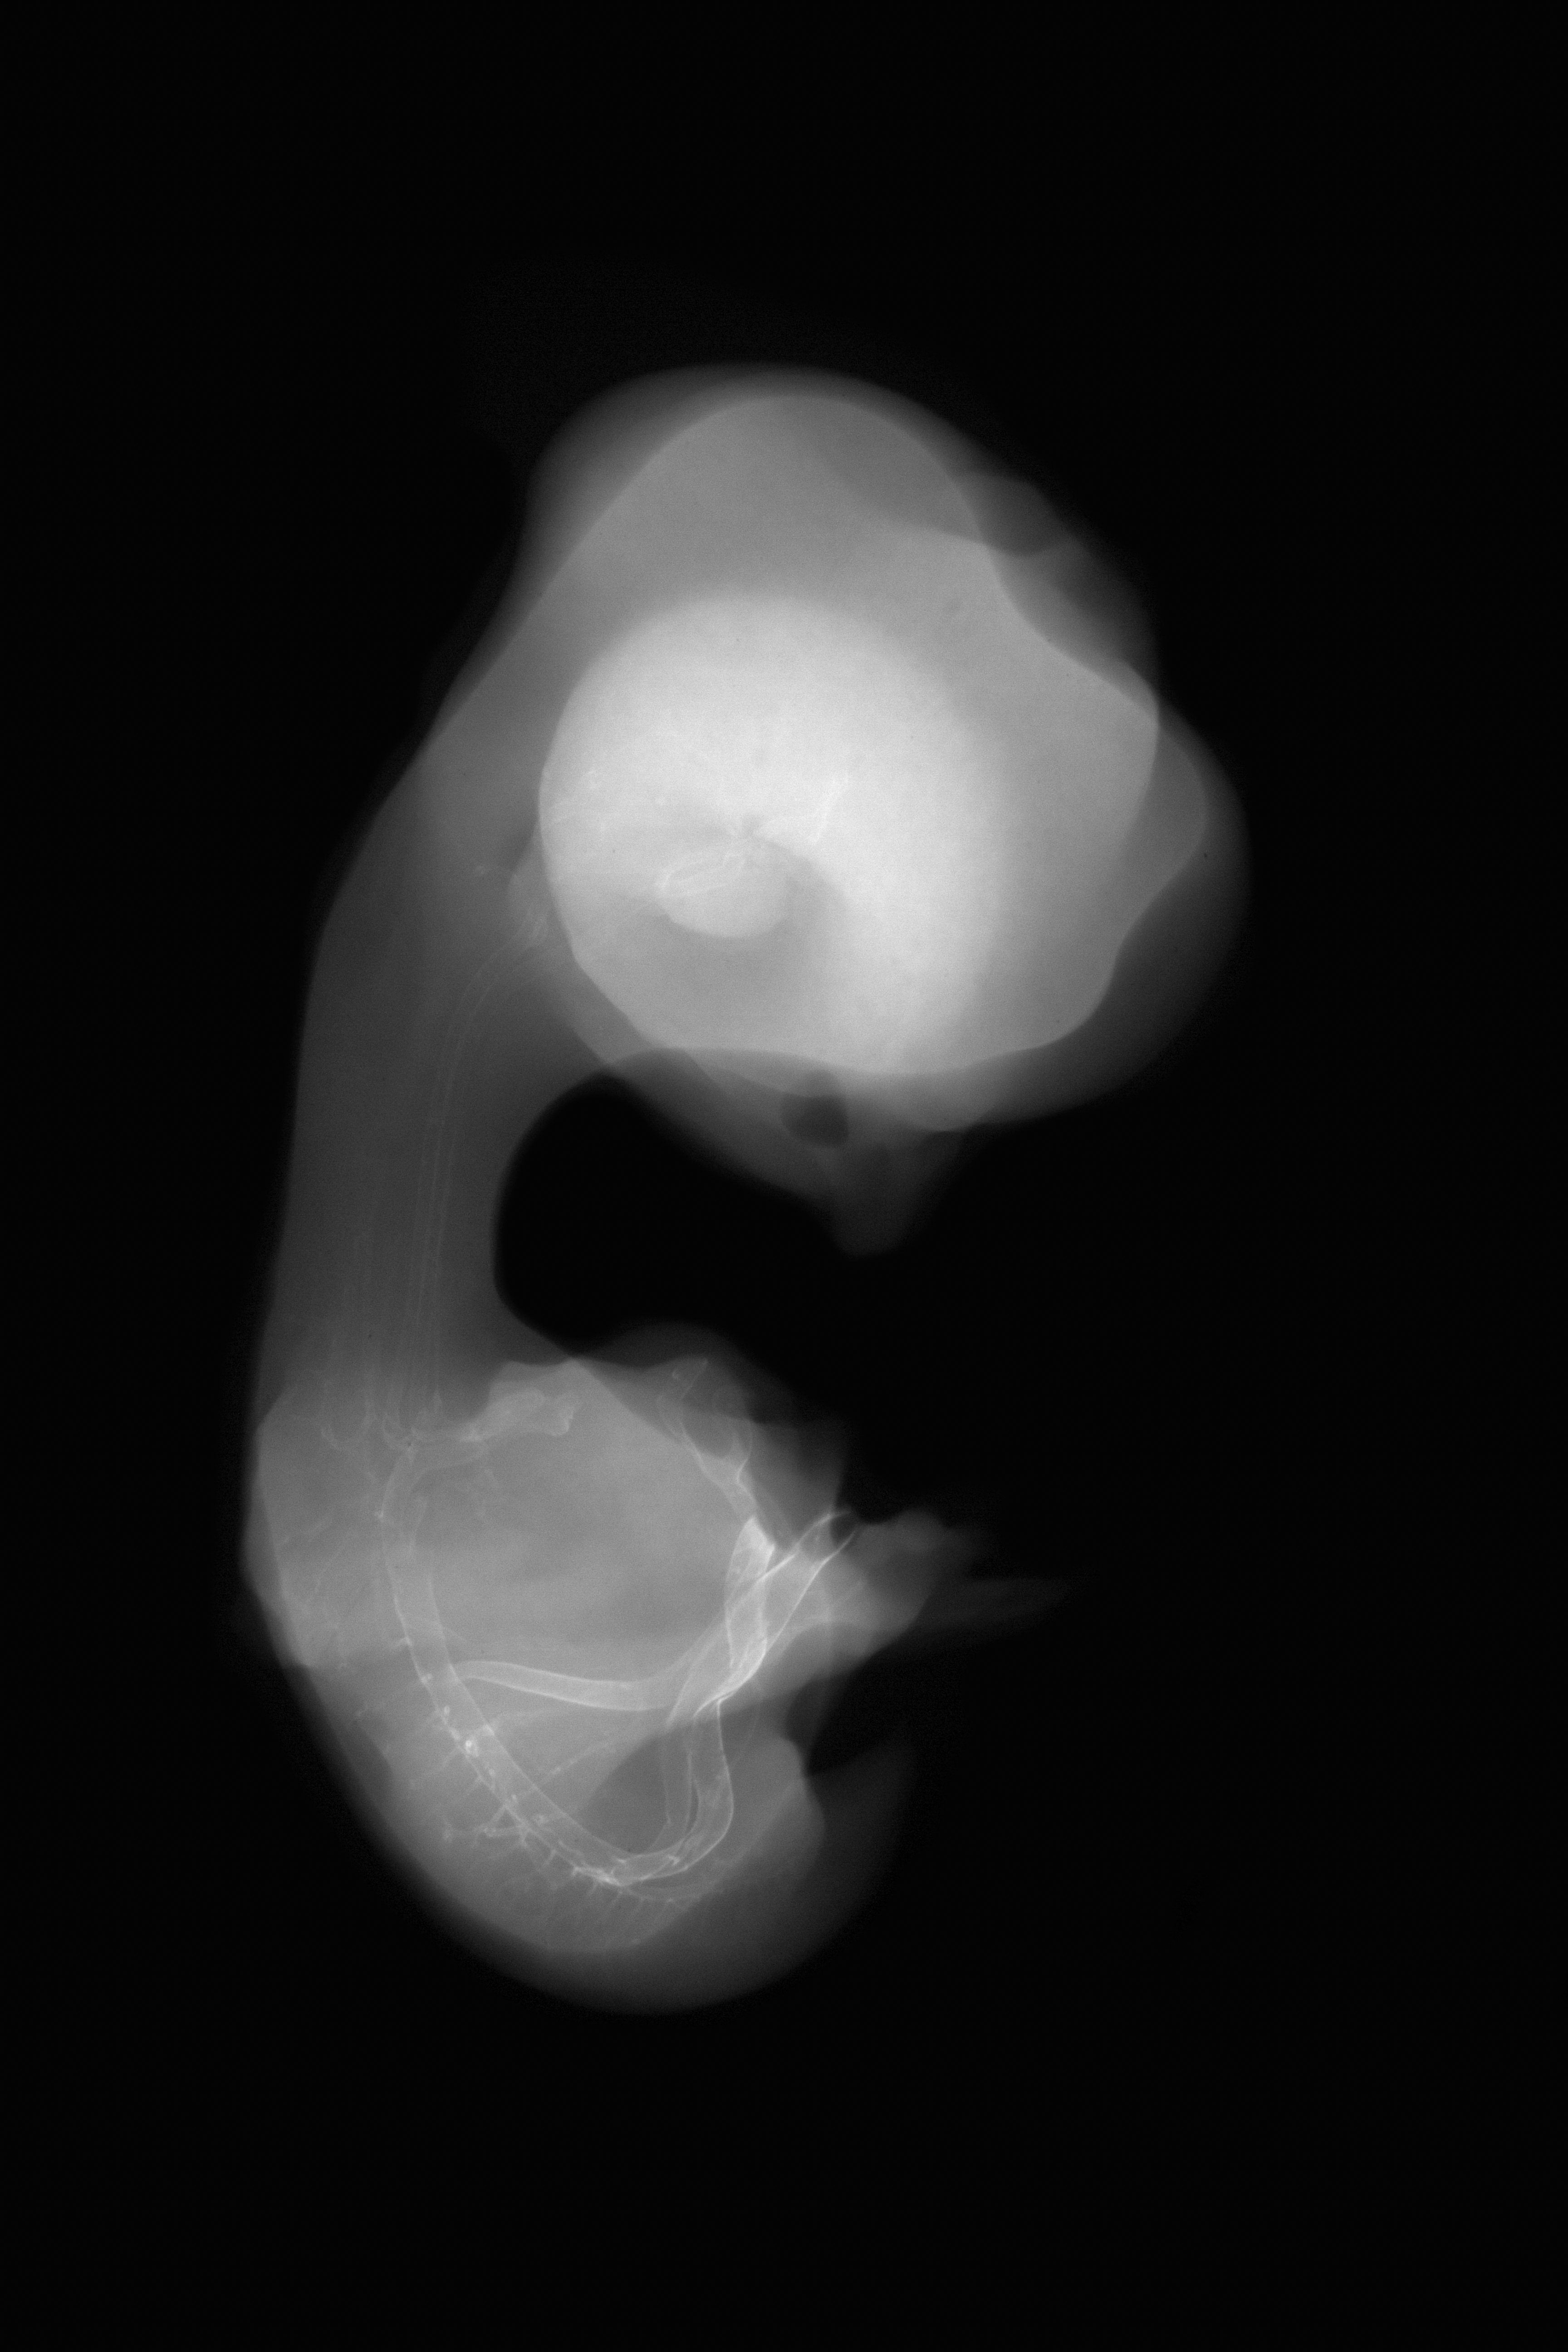

Chick Embryo Microangiography

Hamburger-Hamilton (HH) Stage 31 (approx. 7 days)

X-Ray Micrographs